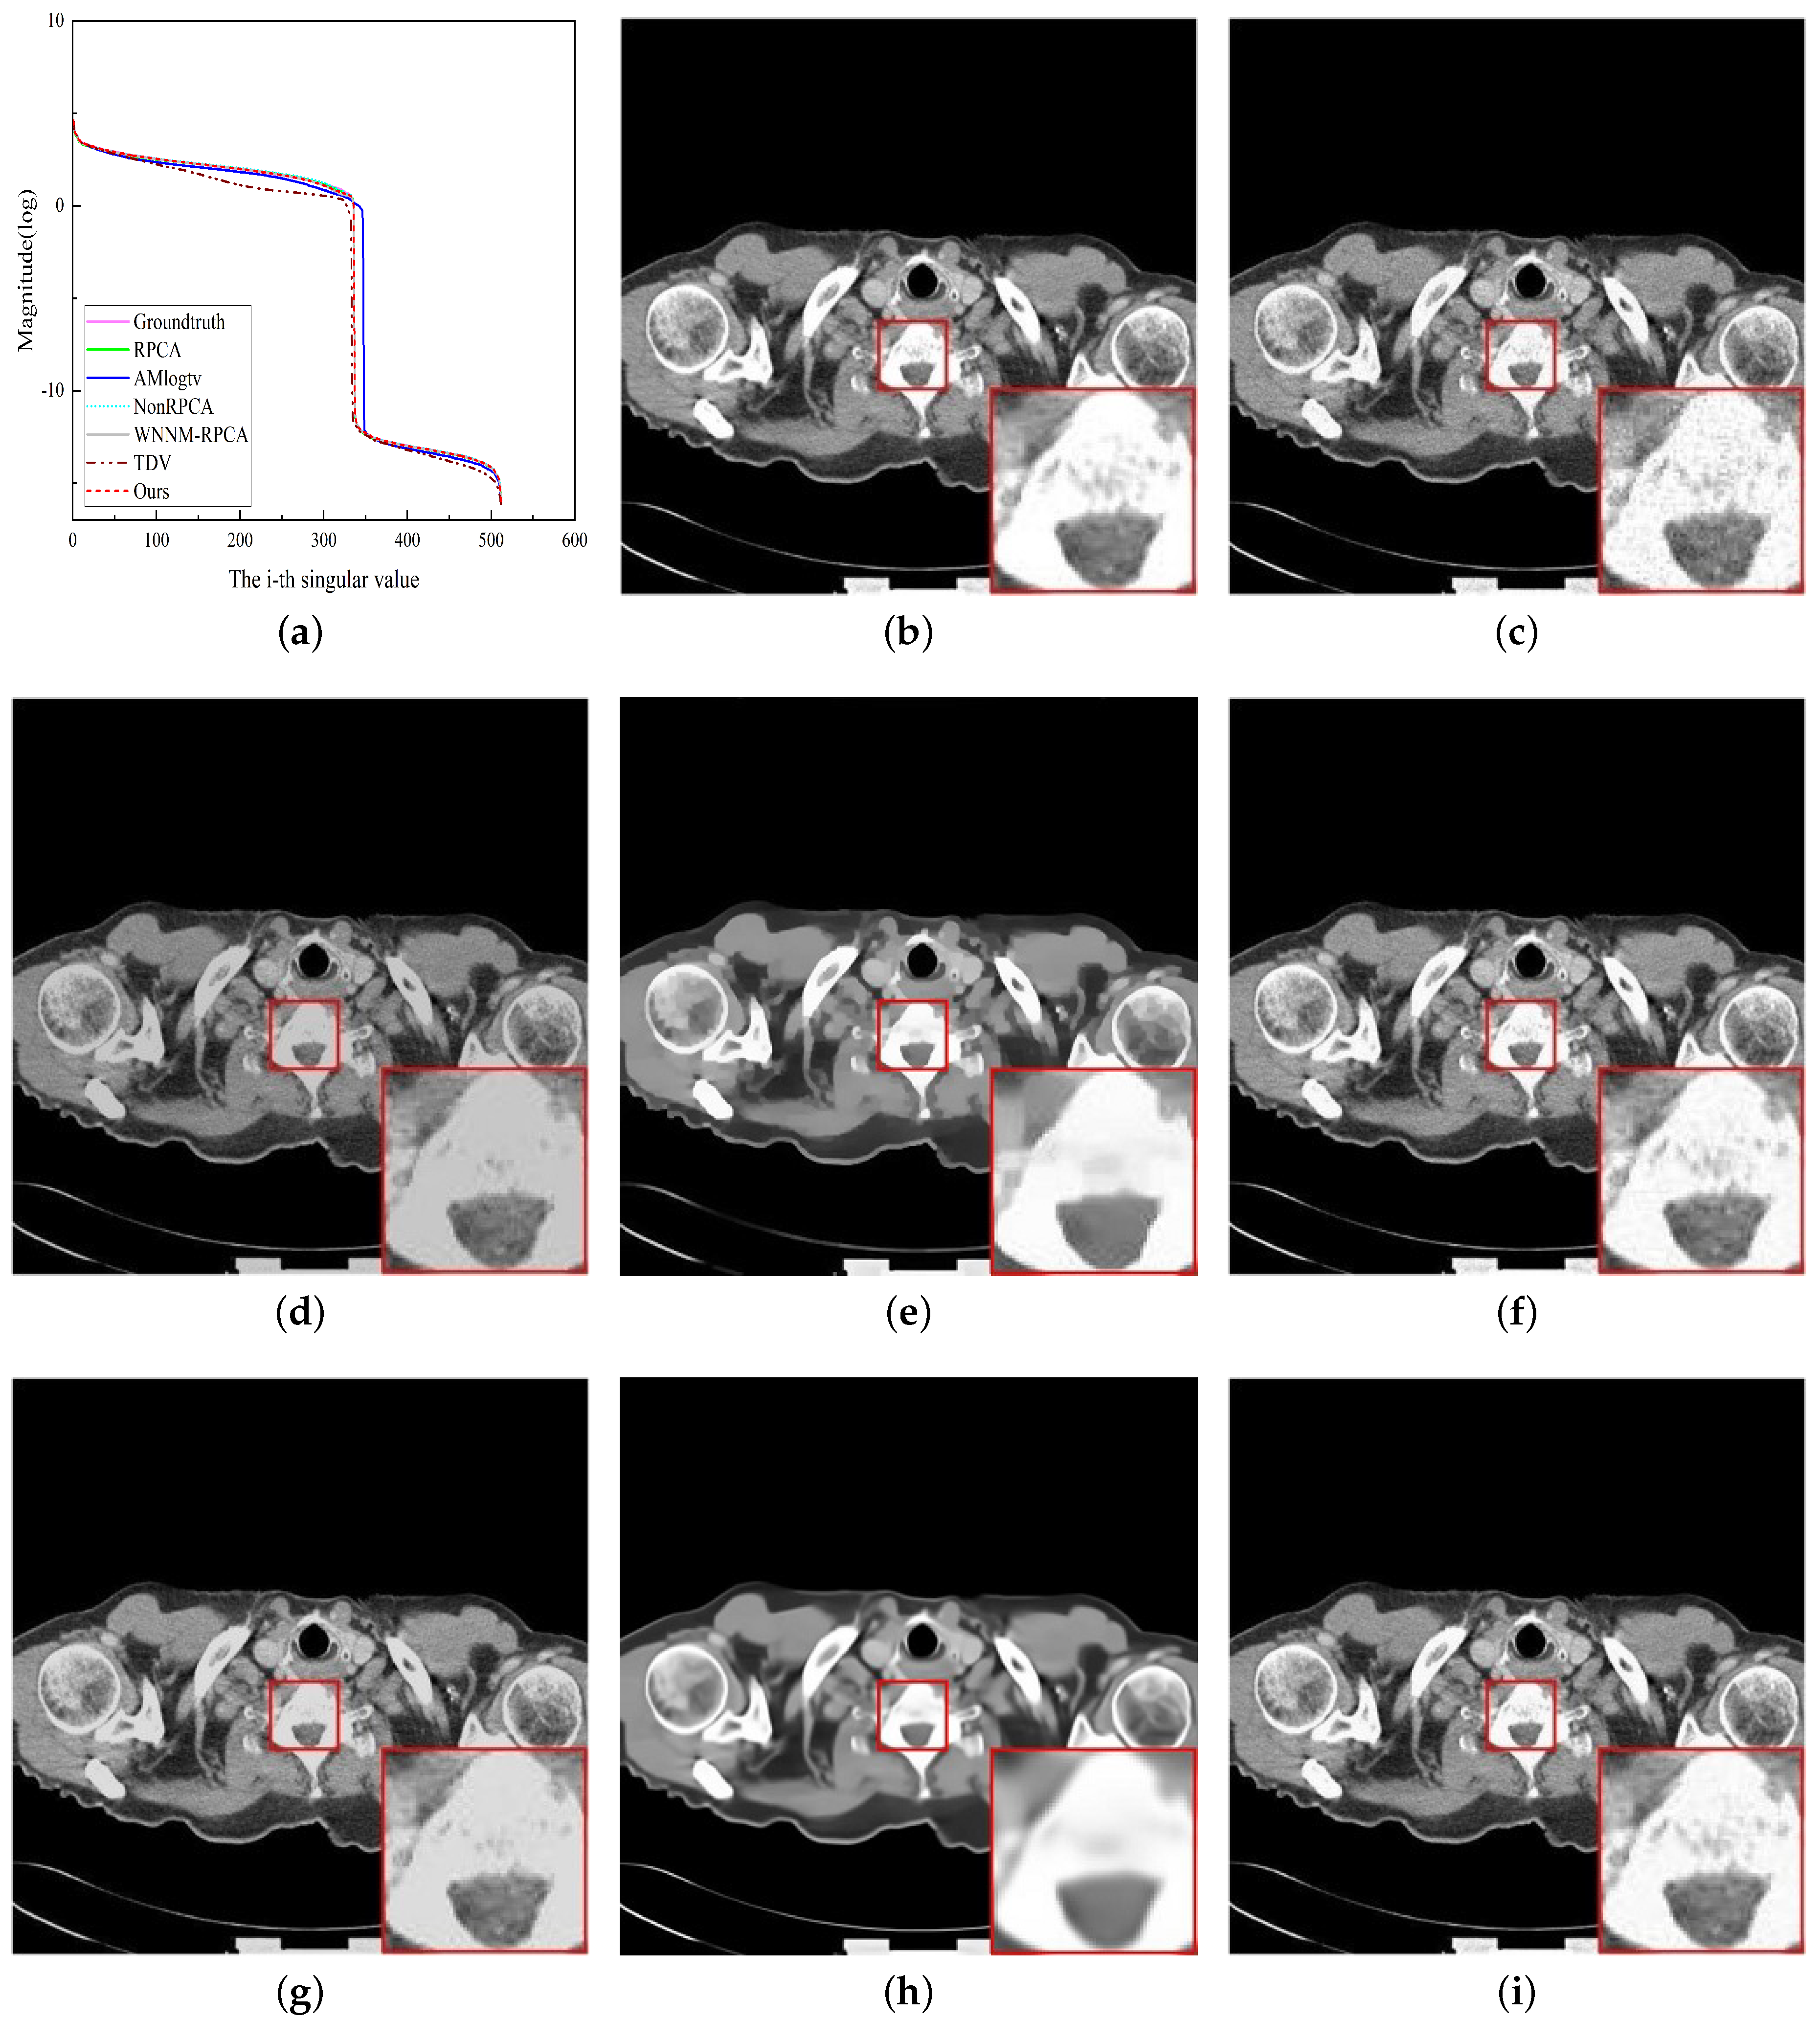

4.2. Medical Image Denoising